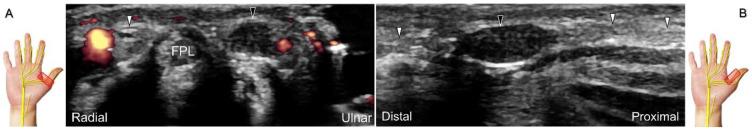

超声已成为一种极具价值的工具,用于腕部区域周围神经病变的成像,特别是对于诸如腕管综合征和尺神经管综合征等常见病症。大量研究表明,神经在卡压部位近端肿胀、边界不清和平扁是神经卡压的特征。然而,关于腕部和手部的小神经或终末神经的信息却很匮乏。本文旨在通过全面概述这些神经卡压的扫描技术、病理学和引导注射方法来填补这一知识空白。本综述详细阐述了正中神经(主干、掌皮支和返支)、尺神经(主干、浅支、深支、掌尺皮支和背尺皮支)、桡浅神经、骨间后神经、掌总/指固有神经和背总/指固有神经。一系列超声图像用于详细说明这些技术。最后,超声检查结果补充了电诊断研究,有助于更好地理解整个临床情况,而超声引导下的干预措施对于治疗相关神经病变是安全有效的。